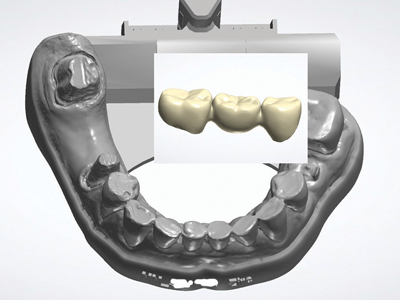

Aesthetic Crown and Bridge Restorations Using a Fully Digital Workflow

crown and bridge

Introduction: The Digital Revolution in Dentistry Whether or not a clinician is working under the model of an in-house chairside milling solution or a more traditional lab-based relationship, digital scanner capture for crown and bridge restorations offers significant advantages over impression based capture – especially when prescribing digitally manufactured restorations. Many esthetic restorative materials are … Read more